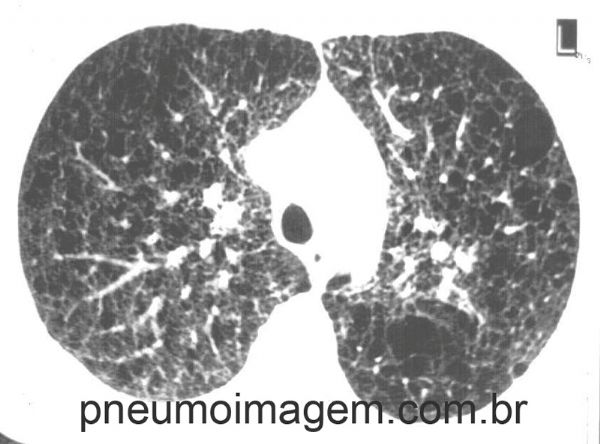

Corte tomográfico em LAM demonstrando cistos de paredes finas com distribuição difusa. Espessamento septal e opacidades em vidro fosco. Pequenos nódulos.

CT scanning in LAM demonstrating thin-walled cysts with diffuse distribution. Septal thickening and ground glass opacities. Small nodules.